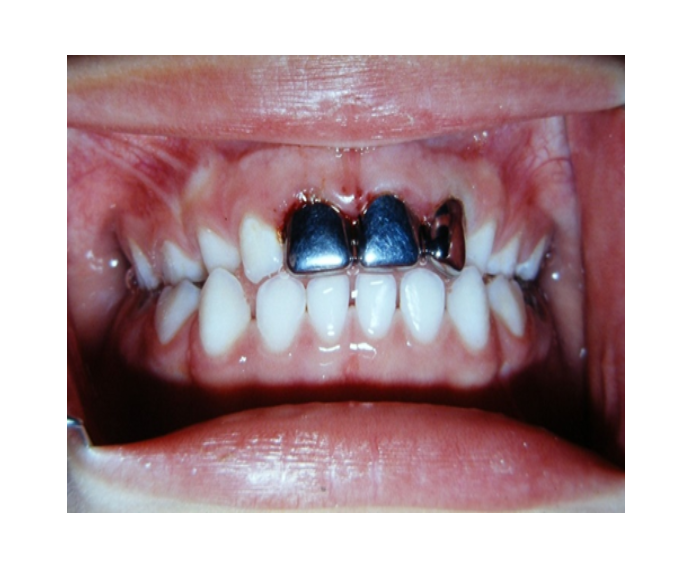

Mordida Cruzada anterior unidental